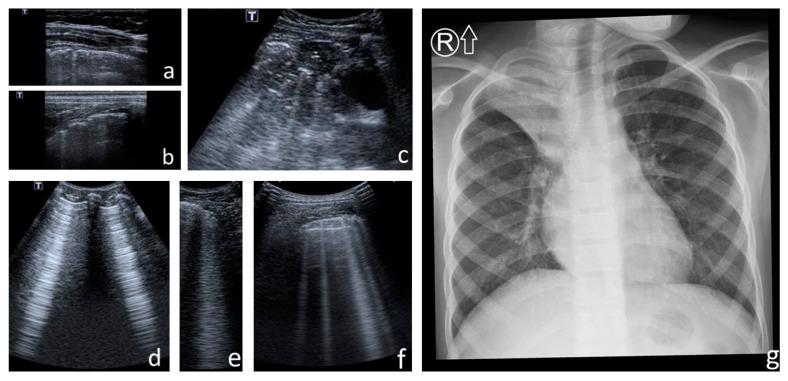

With the increasing longevity of cystic fibrosis (CF), there is a growing need to minimise exposure to ionising radiation in patients who undergo regular imaging tests while monitoring the course of the lung disease. This study aimed to define the role of lung ultrasounds (LUS) in the evaluation of lung disease severity in children with clinically stable CF. LUS was performed on 131 patients aged 5 weeks to 18 years (study group) and in 32 healthy children of an equivalent age range (control group). Additionally, an interobserver study was performed on 38 patients from the study group. In CF patients, the following ultrasound signs were identified: I-lines; Z-lines; single, numerous and confluent B-lines; Am-lines; small and major consolidations; pleural line abnormalities and small amounts of pleural fluid. The obtained results were evaluated against an original ultrasound score. LUS results were correlated with the results of chest X-ray (CXR) [very high], pulmonary function tests (PFTs) [high] and microbiological status [significant]. The interobserver study showed very good agreement between investigators. We conclude that LUS is a useful test in the evaluation of CF lung disease severity compared to routinely used methods. With appropriate standardisation, LUS is highly reproducible.

随着囊性纤维化(CF)患者寿命的延长,在对肺部疾病病程进行监测的同时,尽量减少接受常规影像学检查的患者所受电离辐射的需求日益增加。本研究旨在明确肺部超声(LUS)在评估临床病情稳定的CF患儿肺部疾病严重程度中的作用。对131例年龄在5周至18岁的患者(研究组)以及32例年龄范围相当的健康儿童(对照组)进行了LUS检查。此外,对研究组中的38例患者进行了观察者间研究。在CF患者中,识别出了以下超声征象:I线;Z线;单发、多发及融合的B线;Am线;小实变和大实变;胸膜线异常及少量胸腔积液。将获得的结果与原始超声评分进行对照评估。LUS结果与胸部X线(CXR)结果[高度相关]、肺功能测试(PFTs)结果[相关性高]以及微生物学状态[显著相关]相关。观察者间研究显示研究者之间具有很好的一致性。我们得出结论,与常规使用的方法相比,LUS在评估CF肺部疾病严重程度方面是一种有用的检查方法。通过适当的标准化,LUS具有高度可重复性。